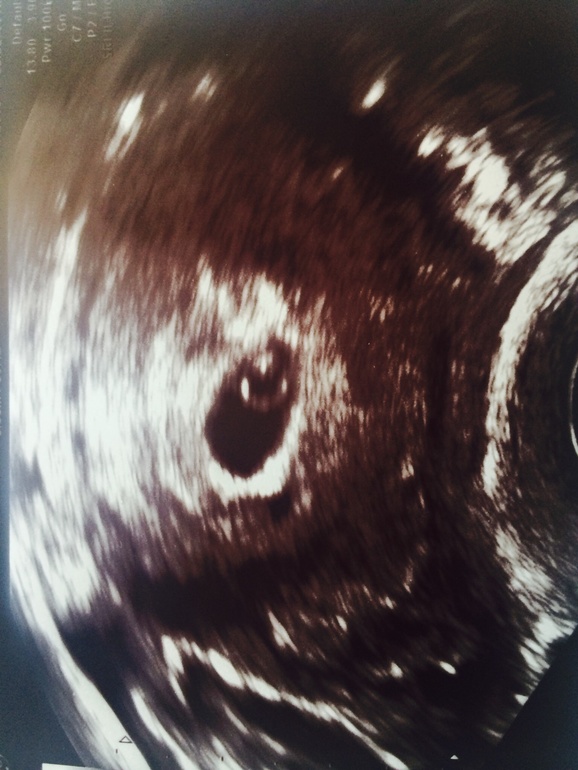

Пусть развивается точечка и сердечко бьется!!!! @@@

Радость!